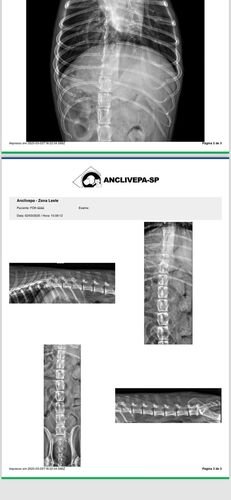

No dia 02 de março de 2025, Fox sofreu um grave acidente. Uma linha de pipa com cerol passou pela laje de casa e cortou a Fox. Assustada, ela caiu da laje de uma altura de 3 metros, sofrendo diversas fraturas nas patinhas e costelas, lesões internas que prejudicaram sua mobilidade.